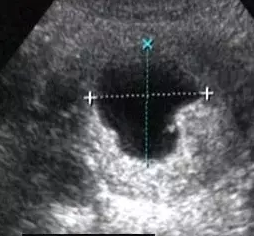

空孕囊

轮廓不规则或有缺损,常小于孕龄呈空虚状,张力差;空孕囊由于胚胎死亡枯萎,可位于宫腔中央或略偏向一侧,一般下移至子宫颈内或宫腔下段;空孕囊随孕龄不生长或生长缓慢。